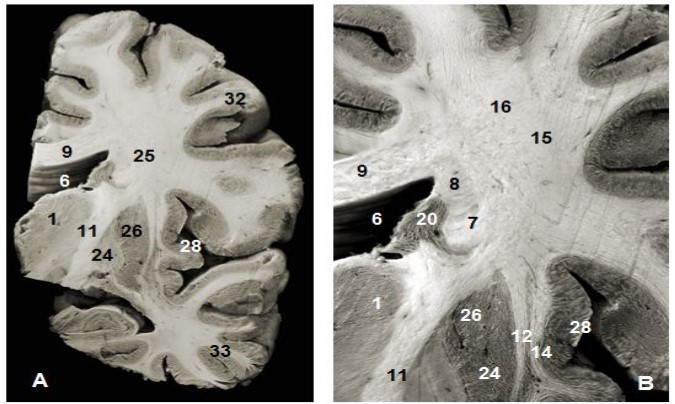

Figure 1.(A) Coronal view of the left hemisphere and (B) global view after magnification and before dissection of (A). 1. Thalamus, 6. Lateral ventricule 7. Subependymal substratum, 9. Corpus callosum, 11. Internal capsule, 12. External capsule, 13. Claustrum, 14. Extreme capsule, 16. Upper branch of the SLF , 20. Head of caudeus nucleus, 23. Putamen, 24. Globus pallidus, 25. Lower branch of SLF 28. Insula, 30. Corona radiata, 32. Parietal pole, 33. Temporal pole.

Anterior and superior thalamocortical pathways course obliquely and connect anterior, mediodorsal, lateral ventral anterior, lateral dorsal and lateral posterior thalamic nuclei to the cerebral cortex. They exposed after the removal of the head and body of the corpus callosum were . A coronal view of the thalamus confirms the course of these fibers to the thalamus. The sub-ependymal stratum and gray matter are medial to the thalamic radiations (Figure 1). The successive excision of the insular cortex, claustrum, fibers of the extreme capsule, the putamen and globus pallidus and pyramidal tract exposed other components lateral to the internal capsule (Figure 1, Figure 4). Fibers of the extreme and external capsules and of the lenticular nucleus (putamen and globus pallidus) formed an inferior relationship with the stem of the uncinate and the inferior occipitofrontal fasciculi. A coronal section through the cerebral hemisphere and the thalamus completed the study of thalamic radiations. The optic radiations and the ventral amygdaloid tract which loop through the anterior perforated substance and the lateral expansion of the anterior commissure sheathed by the Gratiolet canal, which were not include intentionally in our illustrations, were further away. Gratiolet optic radiations connect the thalamus to the geniculate body and the posterior nucleus of the occipital cortex. These thalamic radiations line up the lateral ventricle.

The abscission of the frontal, parietal and temporal opercula exposed the superior longitudinal fasciculus (SLF) which was the first hemispheric and the largest association bundle to be seen and is located medial to the insular cortex. The SLF is an arcuate fasciculus which wraps around the insula and connects the frontal, parietal, occipital and temporal lobes together (Figure 1, Figure 3). It has a superior and an inferior surface, anterior or frontal end, posterior extremity and the lateral and medial margins. The lateral opercular border is flattened and more spread across. Its fibers project to the straight gyrus which was exposed after the withdrawal of the insular arcuate fibers. The medial edge is in contact with the corona radiata. The frontal, parietal and temporal opercula are lateral to the SLF. Ablation of the lenticular nucleus exposed the inferior and medial aspect of the SLF. Superiorly, U-shaped fibers are 13mm away from the cortex at the level of the central sulcus. The anterior extremity is lateral to the fanning end of the uncinate and inferior occipitofrontal fasciculi, then the corona radiata and the frontal horn of the lateral ventricle. This anterior end was lateral to the ventricle and 19,6mm away from the cortex (10-25mm). The posterior extremity was separated from the lateral ventricle by the optic radiations and the tapetum of the corpus callosum.